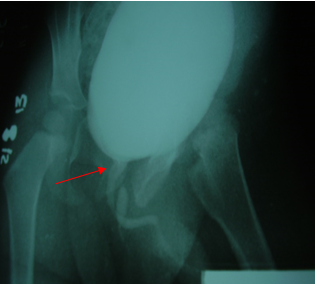

Por lo anterior se discute el caso en el servicio de Urología y se decide realizar estudios de imagen entre estos un ultrasonido urológico sin evidencia ningún tipo de anormalidad; urocultivo sin crecimiento bacteriano; uretrocistografía miccional en donde se observó una vejiga de buena capacidad de características normales y que a la micción puso en manifiesto la presencia de una estructura independiente a la uretra normal dibujándose en toda su trayecto hasta la zona del periné, imagen de aspecto proximal que recuerda la verdadera uretra que va afinándose hasta el final. La uretra verdadera no mostro alteraciones (ver figura 2). En la cistoscopia no se observó anormalidad alguna.

Figura 2 Vejiga de buena capacidad con evidencia de uretra accesoria que desemboca a la región perineal